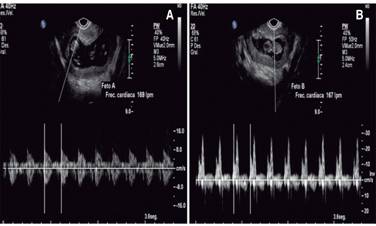

Se presentó al Servicio de Urgencias con los siguientes signos vitales: FC, 80 lpm; FR, 21 rpm; TA, 120/80; T, 37 oC; refería cuadro de dolor abdominal de aparición súbita con aproximadamente siete horas de evolución, constante, en la fosa iliaca derecha (FID), EVA 7/10, irradiado a la región lumbar ipsilateral, vómito en una ocasión de contenido gástrico, sin fiebre, acompañado de náusea y sangrado transvaginal de aproximadamente 15 cm3; negó ingesta previa de medicamentos, así como la presencia de exacerbantes y atenuantes. A la exploración, se encontró abdomen globoso a expensas de panículo adiposo, peristalsis presente, disminuida en la FID; abdomen blando, resistencia muscular voluntaria, doloroso a la palpación superficial, media y profunda en la FID; hiperbaralgesia e hiperestesia dudosas de predominio en la FID; no se palpó crecimiento uterino; dolor en punto de McBurney (+), VonBlumberg (+), Rovsing (-), talopercusión (+). Laboratorios de ingreso, con hemoglobina de 13.2, hematocrito de 38, leucocitos de 26.9, segmentado 95, BUN 10.2, urea 22.1, creatinina 0.58. El USG ginecológico reportó útero gestante de 12.0 × 8.2 × 7.4 cm en sus ejes longitudinal, AP y transversal. En la cavidad endometrial se observaron dos sacos gestacionales de localización normal y apariencia viable, compatibles con embarazo gemelar intrauterino; fondo de saco de Douglas con líquido libre; fosa iliaca derecha en topografía del ciego, se observó asa de paredes levemente engrosadas y peristalsis ausente, líquido libre alrededor; no se pudo descartar proceso inflamatorio apendicular (Figura 1). Se programó apendicectomía laparoscópica; se halló hemoperitoneo de 250 cm3, salpinge derecha aumentada de tamaño, rota y con sangrado activo compatible con embarazo ectópico roto, coágulo organizado en la FID; útero grávido aumentado de tamaño, anexo izquierdo normal, ovario derecho con cuerpo lúteo. Se realizó salpingectomía derecha, evacuación de hemoperitoneo y lavado de cavidad; se colocó drenaje tipo Blacke 19 French (Figura 2); postoperatorio con diagnóstico de embarazo heterotópico roto derecho (Figura 3). La paciente pasó compensada a la Unidad de Cuidado Postoperatorio. Al día siguiente, drenaje con gasto de 85 cm3 serohemático; se realizó un USG obstétrico que reportó vitalidad y viabilidad de los productos fetales intrauterinos (Figura 4). Cuarenta y ocho horas posteriores al procedimiento quirúrgico, se retiró el drenaje y fue dada de alta por los Servicios de Ginecología y Cirugía General. El nacimiento de dos productos, uno del sexo masculino y otro femenino, se llevó a cabo a las 35 SDG mediante cesárea; la indicación de la misma fue preeclampsia desarrollada durante el embarazo. No se presentaron complicaciones durante el procedimiento.

Figura 4: USG obstétrico. (A) Feto A. FC, 169 lpm; 11.3 SDG. Diámetro del saco gestacional de 4.48 cm. Longitud cefalocaudal de 4.7 cm y saco vitelino de 7 mm de diámetro. Movimientos musculoesqueléticos múltiples. Sin anormalidades. (B) Feto B. FC, 167 lpm; 11.2 SDG. Diámetro del saco gestacional de 4.0 cm. Longitud cefalocaudal de 3.7 cm y saco vitelino de 7 mm de diámetro. Movimientos musculoesqueléticos múltiples. Sin anormalidades.